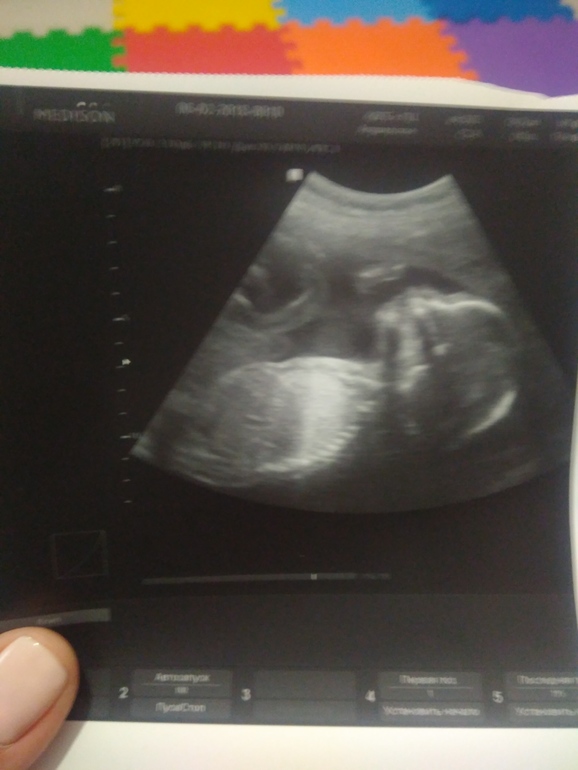

Второе УЗИ,подтвердили девочку))

Наши будни, наши неделькиПо приложению началась 23 неделя,хотя по Узи поставили 20 недель 6 дней вчера, странно,но думаю не очень страшно! Мой малыш размером с баклажан,как говорит мое приложение 🤣Что-то со второй беременностью редко делаю записи, результаты УЗИ все же решила записать) Ох,как нервничала вчера,просто жуть, хоть и не первый раз проходила через это,меня все равно трясло, даже муж волновался ) Да еще врач,которая делает УЗИ -человек настроения. Но! Нам повезло ) Все хорошо,посмотрела,показала, мужа впустила, и ему все объяснила, сделала фото,подтвердила девчонку 😍и НЕ подтвердила мой страшный сон про шесть пальцев на ногах малыша 😬 😲только улыбнулась над моей паникой 😂 🤦♀️Кстати,в первую беременность снился точно такой же сон, что за странные страхи сидят в моем подсознании 💁Сказала,что девочка 💃Все таки у меня есть чутье,сына чувствовала,что мальчик, и сейчас, уже накупила вещичек и боди для девочки,муж волновался - куда это все девать,если будет мальчик 😀Самочувствие в эту беременность хуже, и токс был хуже, и вес больше ((( и сахар на верхней границе, таз уже болит,а еще только пол беременности прошло 😭нос не дышит, проблемы с жкт,как и в прошлый раз! Не люблю быть беременной,только радует пиночки из всего беременного цикла 😍А лупит меня дочь ого-го 🤣Ну почему детки не появляются другим путем 🤣Теперь можно спокойно докупать вещи и выбирать имя,с чем у меня проблемы,ни одно девичье имя в душу не западает, как же завидую тем,кто заранее знает как хочет назвать,и не мучается муками выбора 😆 Вот таки дела, ну и параметры малышки и наша крошка,которая лупила датчик со всей дури,в отличии от сына,который затихал на узи ))))

Бипариетальный размер головки -49, окружность головы - 180 мм

Длина бедренной кости - 35/35

Длина костей голени - 30/30

Длина плечевой кости - 33/33

Длина костей предплечья - 30/30

Кость носа -5,6

Толщина плаценты - нормальная 24,0 мм

20 недель 6 дней

Пдр - 20 июня, по первому УЗИ - 15 июня